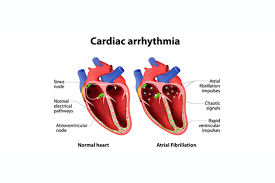

Read MoreCardiac

Cardiac Care focuses on the diagnosis, treatment, and prevention of heart-related conditions, …